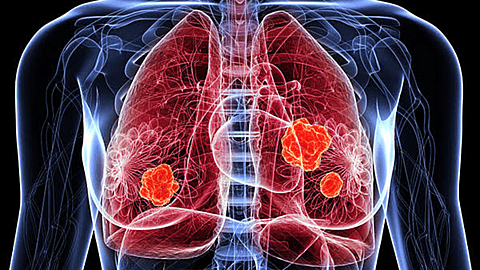

Lung Cancer Awareness Month in November strives to share the stories of survivors. Through their stories of hope, organizations hope to increase knowledge about the disease and its causes. Join Lung Cancer Awareness Month in dispelling myths and improving results.

According to the American Lung Association, lung cancer is the leading cause of death among cancer patients. Luckily, when diagnosed early enough, lung cancer survival rates increase five or more years by almost 56 percent. However, prevention is necessary in order to detect and treat lung cancer before it spreads.

Lung cancer can affect anyone. Because the disease doesn't discriminate, it's important for everyone to review their risk factors. While several high-risk factors attribute to lung cancer a few include air pollution, smoking, exposure to secondhand smoke, and exposure to dangerous chemicals like radon gas.